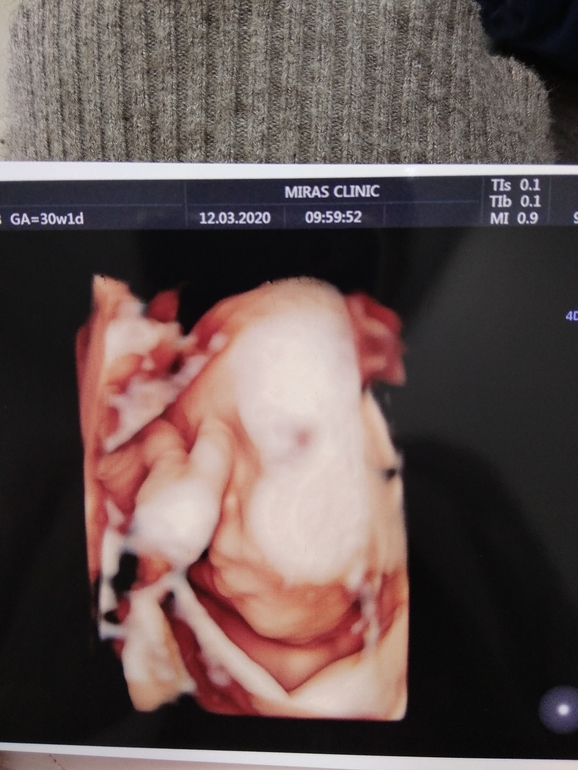

Прошли мы 3 скрининг,все в норме ,но узист сказал контроль желудочков в мозге через 2 недели 9мм они.В остальном сказал ребёночек богатырь 1,950 кг все показатели в норме,у меня тоже все хорошо тьфу тьфу шов норма шейка и плацента тоже.Ну и фото на память моего щекастого мальчишки